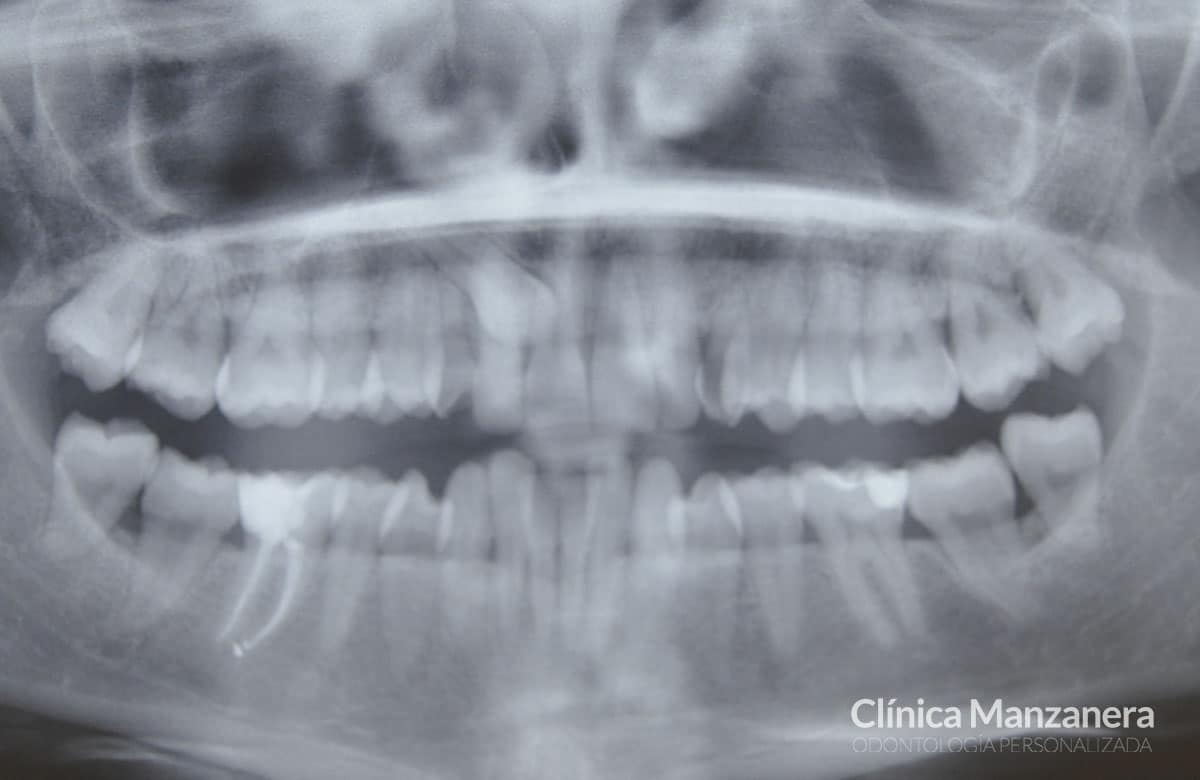

Inicialmente, presentaba una situación con varios elementos que complicaban el tratamiento como podéis ver en las fotos: presencia de un canino incluido (colmillo derecho), ausencia del canino izquierdo, apiñamiento inferior severo, compresión de la arcada superior e inferior (paladar estrecho), y grandes recesiones gingivales (pérdida altura de la encía) en los incisivos centrales inferiores.

Sonrisa antes